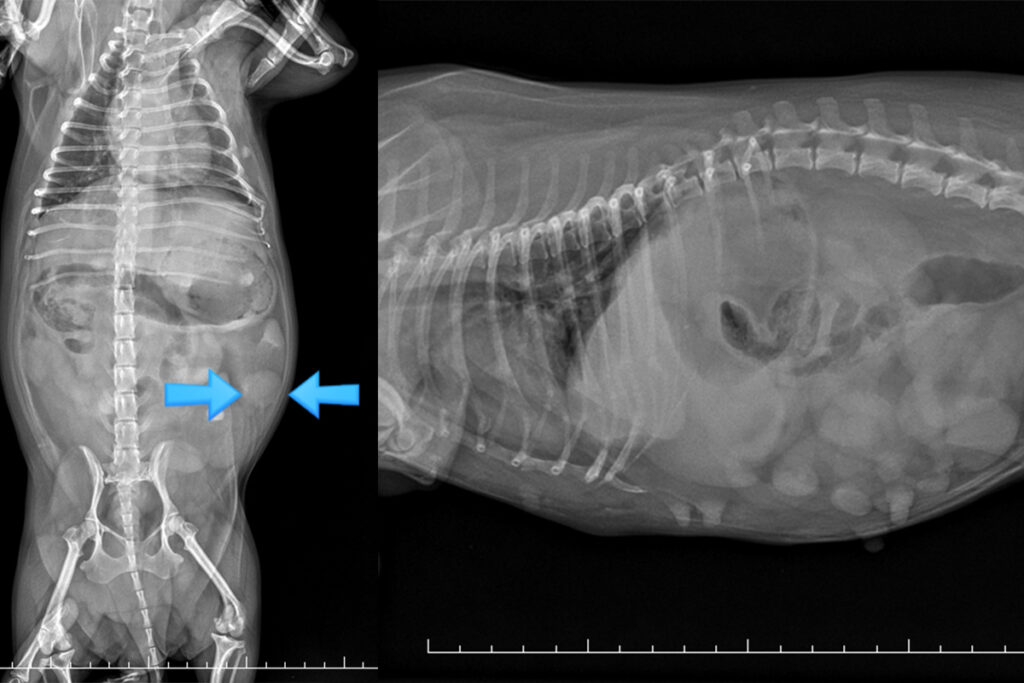

방광 결석 수술

요로 폐색이나 반복적인 통증을 유발하는 결석을 제거하는 수술입니다. 결석 유형과 방광 상태를 고려해 재발 위험까지 함께 관리합니다.